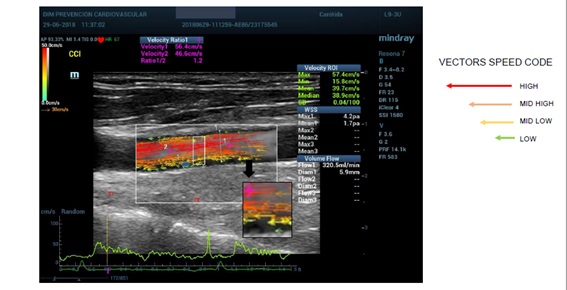

Some studies, performed to analyse the flow in the carotid arteries, showed that the development of arterial plaques is more frequent in the presence of a vortex flow. Colour Doppler (CD), for evaluation of flow patterns, and spectral Doppler analysis (PW), for measurement of blood velocities, have been used to detect flow disturbances in the carotid bifurcation. Although these studies showed that complex flow patterns are detectable, CD and PW are angle-dependent and only estimate the axial component of blood flow velocity; consequently, the quantification of complex flow is not achievable with conventional ultrasound (US) systems. Moreover, CD is also affected by a limited frame rate, allowing low temporal resolution; PW displays the complete spectrum of velocities through the cardiac cycle, but related to a small sample volume and along a single line only. These limitations explain why, in the last decades, the flow complexity analysis was not used for clinical diagnosis or for long-term prognosis and the Doppler evaluation of abnormal flow velocity has been restricted only to the grading of vessel stenosis (Figure 1) [4].

Figure 1: Different ultrasound approaches to study arteries structure and function.

V Flow detects the speed and direction of all blood cells flowing through every point of the Region of Interest (ROI). There are low-speed cells, high-speed blood cells, and reversecells flowing through a point in a short moment. It means that the speed measured and displayed by V Flow in a point is the average speed of all blood cells in a precise short moment. Spatiotemporal characteristics of flow was evaluated visually and quantitatively to asses the specific flow patterns. VFI shows velocity vectors, streamline distribution and vorticity distribution. (Figure 2).

Figure 2: Vector flow imaging.

The streamline distribution uses arrows to indicate the flow direction. The colour and length of the arrows showed the flow velocity, magnitude and direction (green means low velocities, yellow and orange medium velocities and red higher velocities; the longer the arrows the faster the flow). For quantitative evaluation, velocity curves were available: the maximum velocity vector point curve, automatically detected by the system, and the user-defined vector point curve. Both were displayed at the bottom of the image and showed the fluctuating velocities of the flow varying in subsequent cardiac cycles (Figure 3) [12].